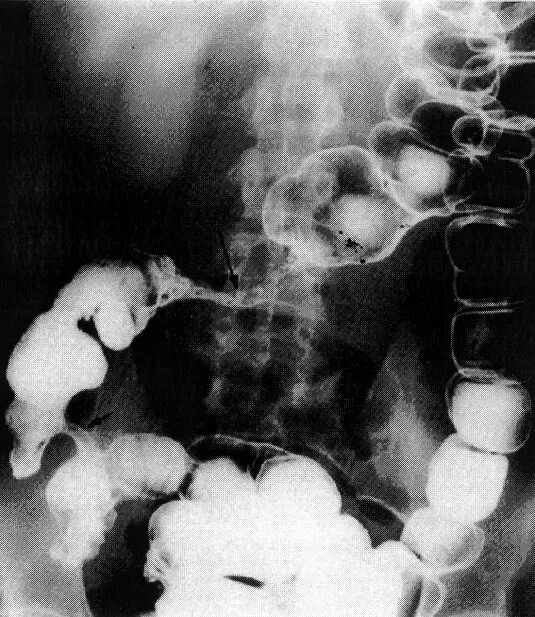

Ирригоскопия с двойным контрастированием